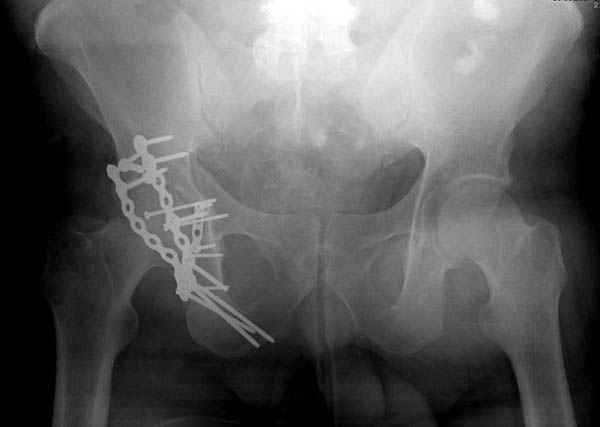

Дополнительно имеется перелом ацетабулума: задняя

колонна с полупоперечным переломом, и переломы костей лица.

На седьмой день зафиксирован перелом ацетабулума через задний доступ.

Имя     : 4 proximal hum +acetabulum.jpg

Тип     : image/jpeg

Размер  : 19494 байтов

Описание: отсутствует

Url     : http://weborto.net:8080/pipermail/ortho/attachments/20071129/c86944d4/attachment-0009.jpg

Имя     : 6 proximal hum +acetabulum iliac.jpg

Размер  : 19051 байтов

Url     : http://weborto.net:8080/pipermail/ortho/attachments/20071129/c86944d4/attachment-0010.jpg